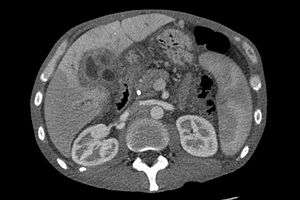

Ultrasound of the liver and biliary tree is often used as the initial imaging modality in patients with suspected obstructive jaundice.[41][42] Ultrasound can identify obstruction and ductal dilatation and, in some cases, may be sufficient to diagnose cholangiocarcinoma.[43] Computed tomography (CT) scanning may also play an important role in the diagnosis of cholangiocarcinoma.[44][45][46]